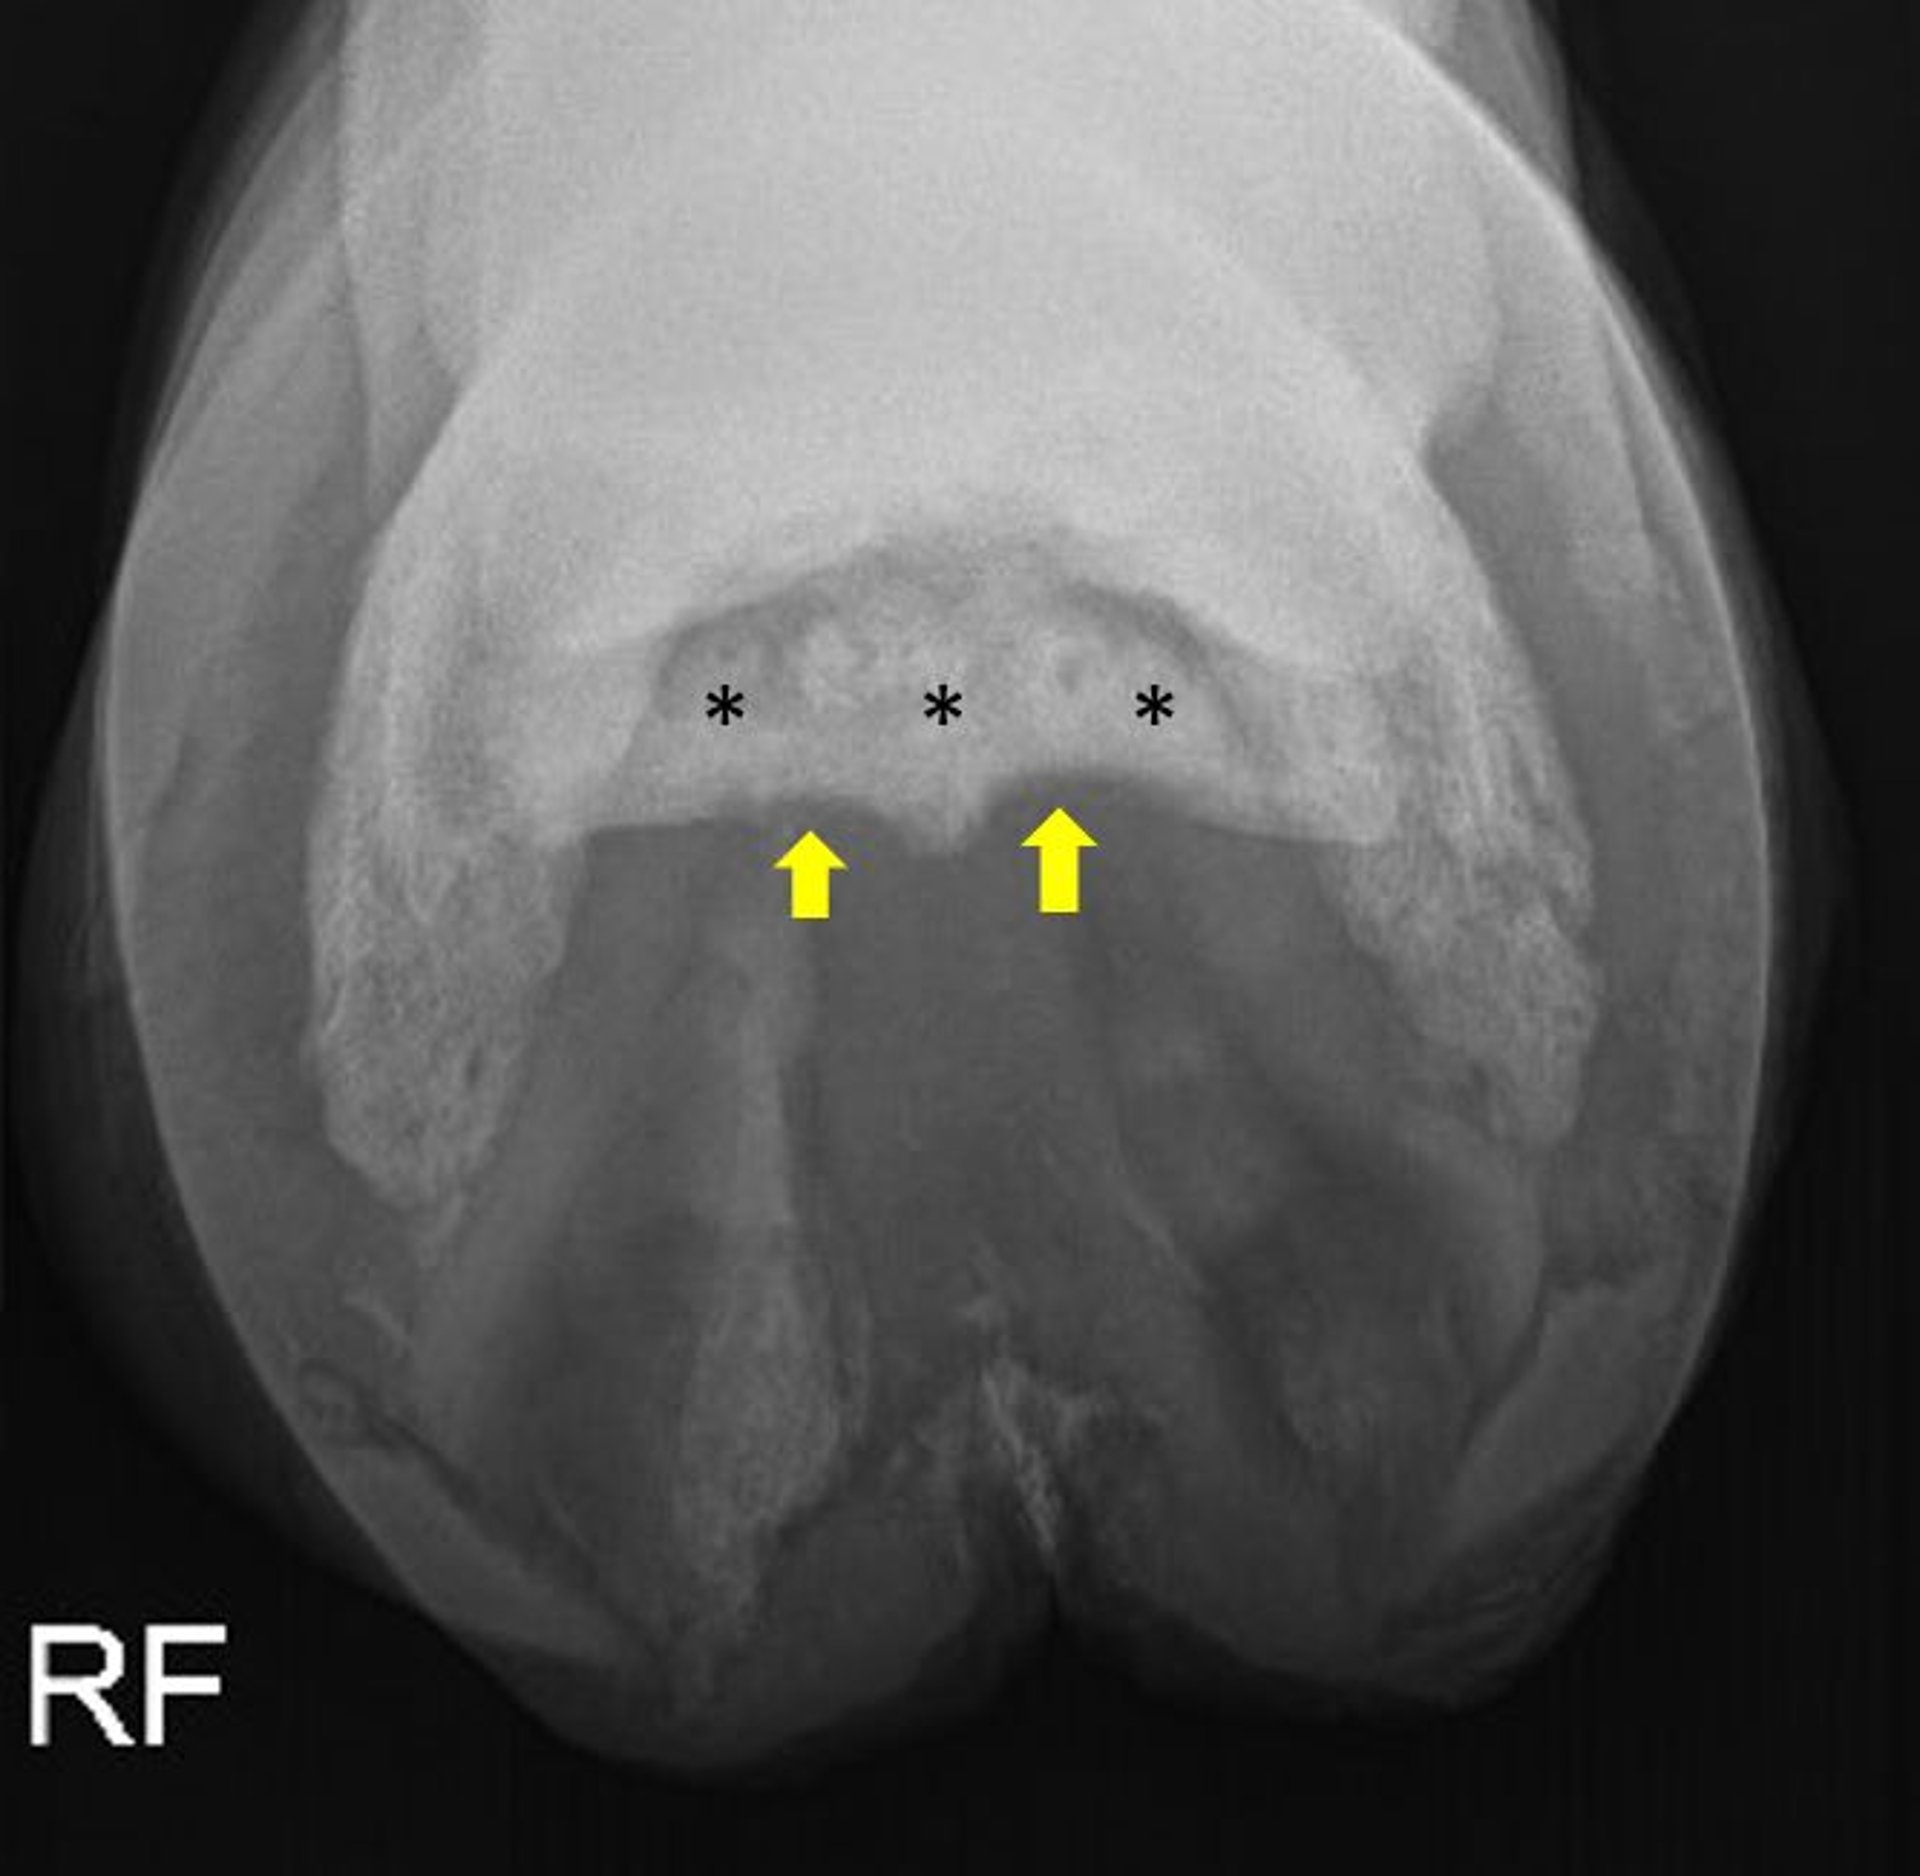

Degeneración del hueso navicular, radiografía, caballo

Radiografía oblicua palmaroproximal-palmarodistal (línea del horizonte) que muestra un hueso navicular gravemente degenerativo en un caballo. Obsérvese la pérdida de la distinción corticomedular (asteriscos), así como la esclerosis de la cavidad medular (asteriscos) y la erosión de la corteza flexora (flechas).

Cortesía de la Dra. Valerie J. Moorman.